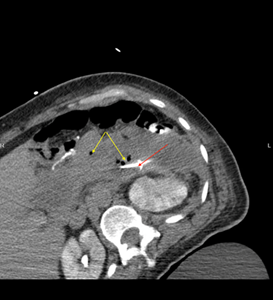

each and was continued on meropenem. STAT CT abdomen and pelvis was performed

which showed enhancing pancreatitis with slightly larger necrotic pancreatic

wall, now containing multiple pockets of air concerning the superimposed

infection, abscess or the fistulation to adjacent bowel. IR guided drainage and

Jackson-Pratt (JP) drain placement showed purulent collection (Figure 3).

She was continued on meropenem for antibiotic and started improving transiently

with coming off pressors next day of drain placement

Figure 3: CT image showing multiple air

pockets (Yellow arrow) and JP drain placement (Red arrow)